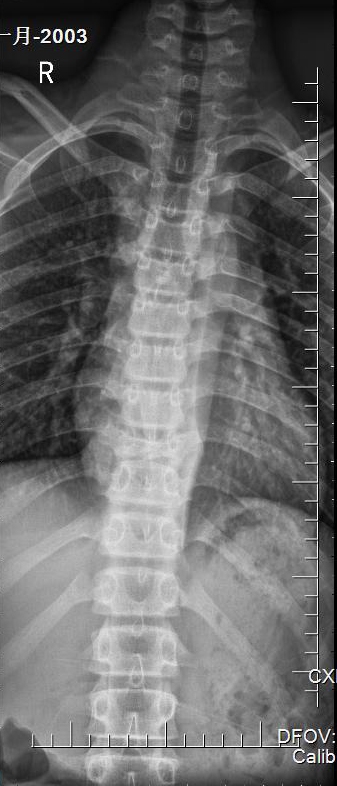

入院X片:胸9楔形改变,椎体高度损伤80%。

入院胸椎X片